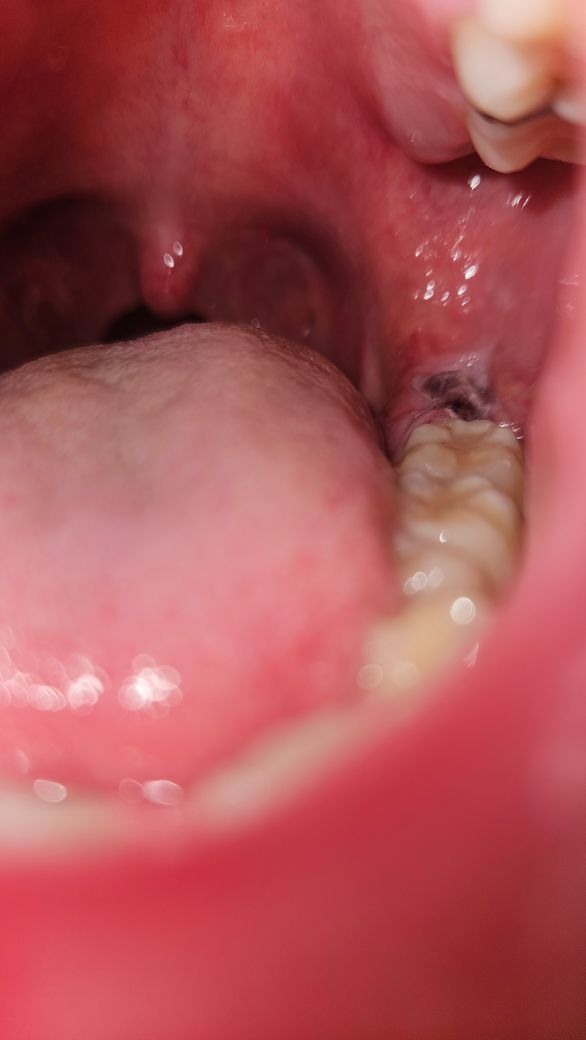

사랑니 발치 후 상태 관련 질문드립니다.

매복 사랑니 월요일에 발치하고 개인사정 때문에 이르게 오늘(목요일) 아침에 실밥을 뽑고왔습니다. 지금 잘 낫고 있는 상태인건가요?

• 1번 째 사진

사진상 문제 될 것은 안보입니다. 추후 통증이 극심해지거나 냄새가 심하게 난다면 치과 가보시면 됩니다.

사진으로만 봤을 경우에는 발치려고 발치한 부위 혈병이 잘 차이는 것으로 보입니다.

혈병에 제거가 되면 치료가 늦어질 수 있기 때문에 해당 부위가 자극되지 않도록 해 주는 것이 좋습니다.

사진상으로 보면 상처가 잘 치유되고 잇습니다. 아직 상처가 다 아문건 아니니 양치를 너무강하게만 하지 마세요.

현재 잘아물고 있는 것으로 보이기에 크게 걱정하지 않으셔도 됩니다.

큰 무리 없이 잇몸 치유가 진행되고 있는 것 같습니다. 다만, 아직까지 완전히 구멍이 메워지지 않았으므로 해당부위로 음식물이 잘 낍니다. 양치질을 살살 해주어 낀 음식물을 잘 빼주시고 그래도 관리가 어렵다면 워터픽이나 주사 시린지로 물을 쏴서 약한 압력으로 음식물을 빼주셔야 합니다.